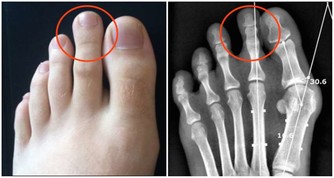

1.指甲

健康指甲,通常因血液提供充分而呈桃紅色,表面光滑圓潤,厚薄適量,形狀平滑光潔,無縱橫溝紋,沒有乾擾斑。若肝血盛衰呈現變化,往往會在指甲上會有表現。

辨顏色:若指甲顏色蒼白,往往講明有貧血或營養不好;若指甲黯黃,也許是肝膽病症或其他慢性病症的先兆,需進一步體檢才可以診斷出;指甲青紫,暗示有寒症,或是血瘀、缺氧。

辨斑點:指甲呈現白色斑點,多為小兒吸收不好、蟲積或者缺鈣,日常應重視飲食衛生和營養物質均衡;指甲下呈現紅色斑點,講述明毛細血管有出血;呈現黑斑,講述明血液循環出現障礙,也許有腫瘤、壞疽,建議到醫院做進一步體檢醫治。

辨紋路:通常指甲呈現縱紋,多為過量勞累、神經衰弱、免疫力低下或其他慢性病症,日常應重視休息;呈現橫溝,通常是營養物質不好,或是慢性吸收系統病症。